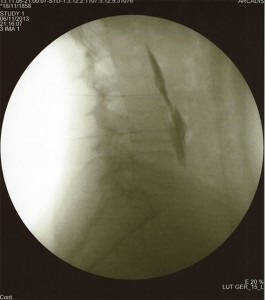

TÉCNICA

Paciente en decúbito prono, con una almohada en abdomen para disminuir la lordosis fisiológica. Con el arco de fluoroscopia en en posición AP  se localiza el espacio a tratar y con un marcador radiopaco se localiza y señala en la piel el punto de punción. Se moviliza el arco de rayos en dirección cráneo-caudal para eliminar el doble contorno. Se prepara la zona de punción con antiséptico, y se infiltra la piel, el tejido celular subcutáneo y los planos musculares con anestésico local. Se realiza la inyección con una  aguja de Tuohy hacia el target desde 2 cuerpos vertebrales inferiores al nivel de entrada en el espacio epidural. Se localiza el espacio epidural con la técnica de pérdida de resistencia y se inyecta contraste radiológico en visión directa (epidurograma). A continuación se coloca el arco de fluoroscopia en  en posición lateral para comprobación de la correcta colocación de la aguja y distribución del contraste. Se vuelve el arco de fluoroscopia a la posición anteroposterior y se inyecta la medicación (anestésicos locales y esteroides).